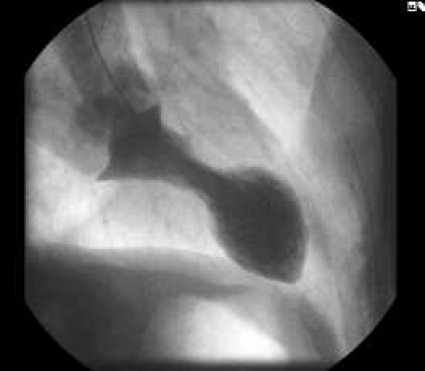

Man får gå tillbaka till 1990 för att finna den ursprungliga beskrivningen av denna variant av kardiomyopati. Sato och medarbetare i Hiroshima i Japan beskrev då ett tillstånd som innefattade ett insjuknande som vid akut hjärtinfarkt, systolisk vänsterkammardysfunktion (vanligen drabbande apikala halvan av vänster kammare) och frånvaro av förträngningar i kranskärlen [2]. Man noterade också att majoriteten av patienterna var kvinnor och att insjuknandet sammanföll med att de varit utsatta för emotionell stress. Vid ventrikulografi liknar den apikalt dilaterade vänsterkammaren en takotsubo, bläckfiskfälla (Figur 1), som därför fick ge namn åt denna variant av kardiomyopati. I litteraturen förekommer andra benämningar, såsom »apikal ballonering av vänster kammare« [3] och »ampullakardiomyopati« [4]. Kopplingen till emotionell stress har också resulterat i termer som »stresskardiomyopati« [5] eller »det brustna hjärtat« [6]. Västvärldens uppmärksamhet kring detta tillstånd väcktes efter en artikel publicerad 2005 i New England Journal of Medicine, där Wittstein och medarbetare rapporterade en studie på 19 sjukhusvårdade patienter med stressutlöst, reversibel vänsterkammardysfunktion [5]. Hos dessa patienter uppmättes vid ankomsten 2–3 gånger högre nivåer av katekolaminer i plasma än hos ålders- och könsmatchade patienter med akut hjärtinfarkt. Författarna konkluderade att katekolaminer tycks vara centrala i den bakomliggande patofysiologin vid stressutlöst, reversibel vänsterkammardysfunktion. Med följande fallbeskrivningar vill vi uppmärksamma takotsubo-kardiomyopati som en möjlig differentialdiagnos till akut hjärtinfarkt.